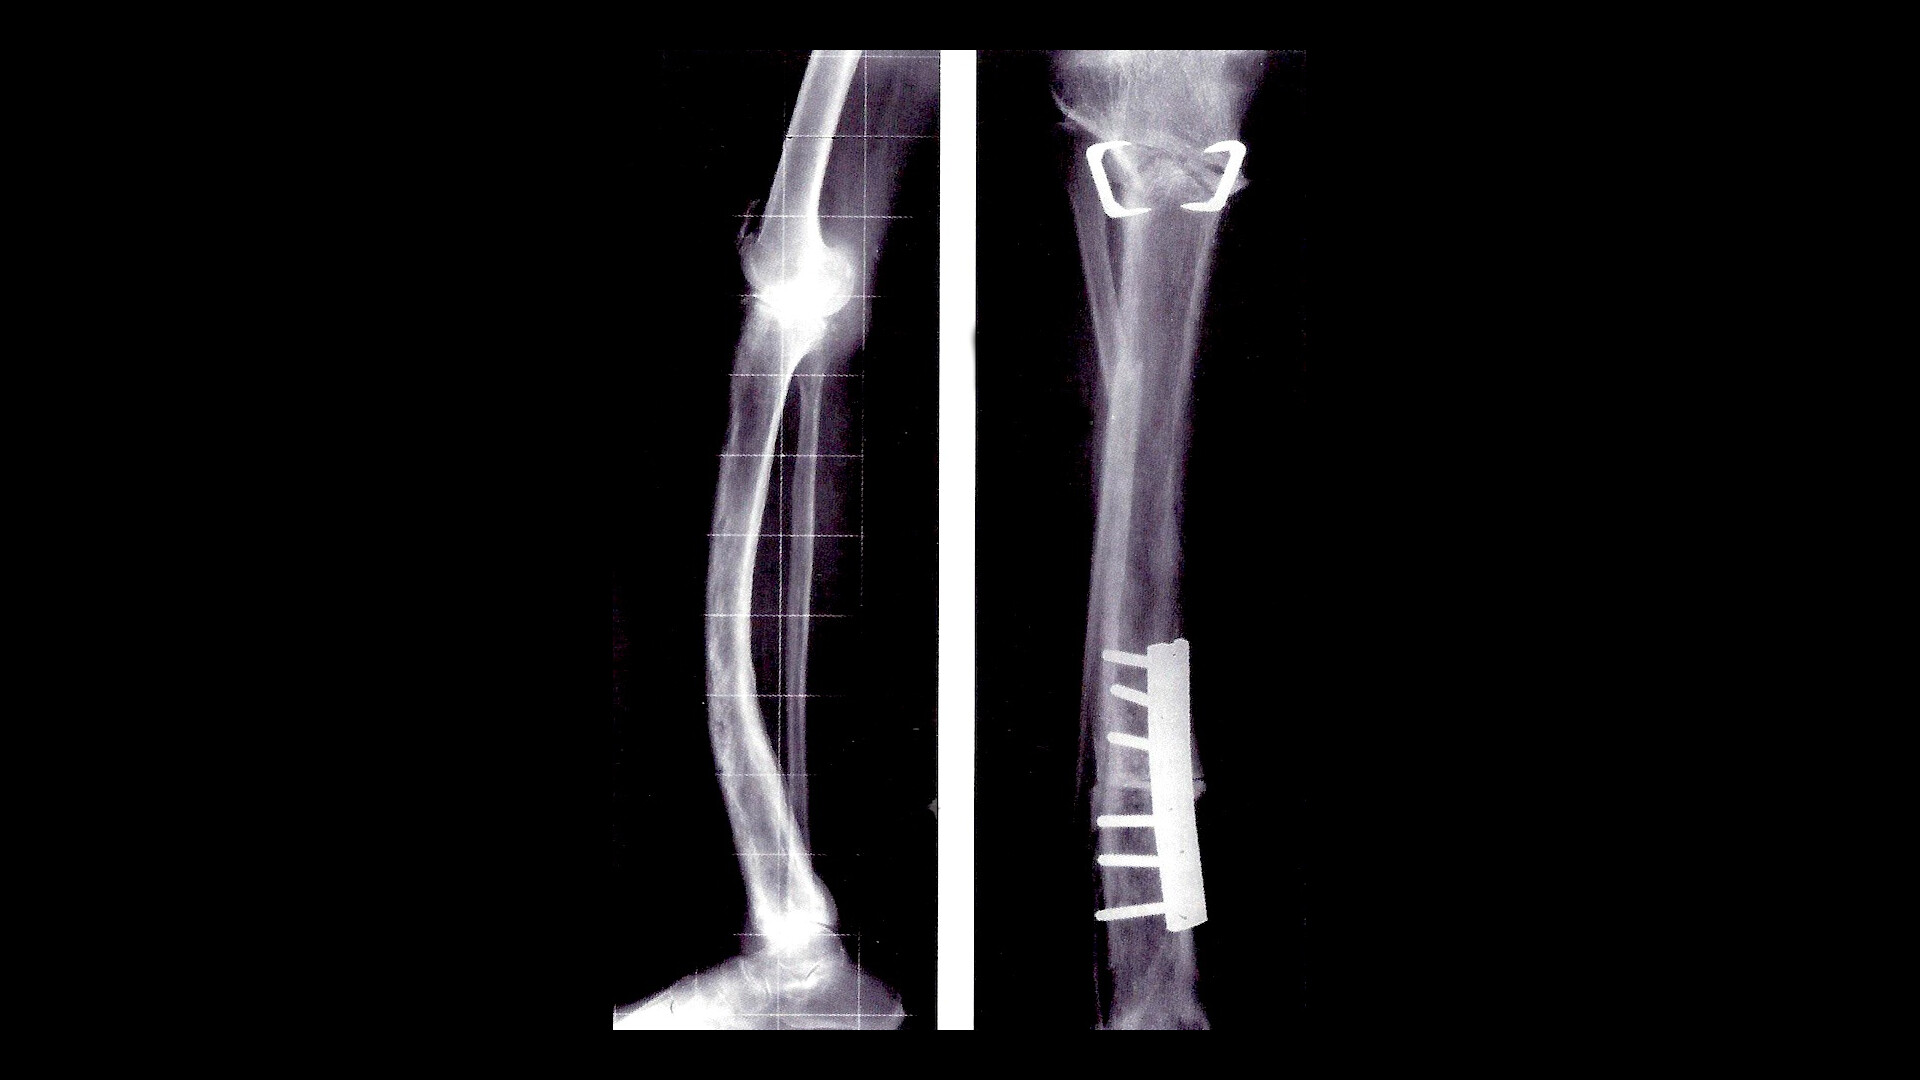

Juvenile Paget Disease. This condition causes bones to be abnormally. juvenile paget's disease, an autosomal recessive osteopathy, is characterized by rapidly remodeling woven bone, osteopenia, fractures, and progressive skeletal deformity. juvenile paget disease is a very rare form of paget disease of the bone characterized by a general increase in bone turnover with. juvenile paget disease (jpd) is a rare disorder, mainly caused by mutations in the gene tnfrsf11b that encodes. learn about juvenile paget disease, a disorder that causes abnormal and weak bones in infants and children. juvenile paget disease is a very rare form of paget disease of the bone characterized by a general increase in bone turnover with. paget’s disease of bone (pdb) is the second most prevalent metabolic bone disorder worldwide, with a prevalence rate. juvenile paget disease (jpd) is a rare disorder, mainly caused by mutations in the gene tnfrsf11b that encodes. juvenile paget disease is a very rare condition that affects bone growth.

juvenile paget disease (jpd) is a rare disorder, mainly caused by mutations in the gene tnfrsf11b that encodes. juvenile paget disease (jpd) is a rare disorder, mainly caused by mutations in the gene tnfrsf11b that encodes. juvenile paget's disease, an autosomal recessive osteopathy, is characterized by rapidly remodeling woven bone, osteopenia, fractures, and progressive skeletal deformity. This condition causes bones to be abnormally. juvenile paget disease is a very rare condition that affects bone growth. learn about juvenile paget disease, a disorder that causes abnormal and weak bones in infants and children. juvenile paget disease is a very rare form of paget disease of the bone characterized by a general increase in bone turnover with. paget’s disease of bone (pdb) is the second most prevalent metabolic bone disorder worldwide, with a prevalence rate. juvenile paget disease is a very rare form of paget disease of the bone characterized by a general increase in bone turnover with.

Juvenile Paget Disease This condition causes bones to be abnormally. juvenile paget disease is a very rare condition that affects bone growth. paget’s disease of bone (pdb) is the second most prevalent metabolic bone disorder worldwide, with a prevalence rate. juvenile paget disease is a very rare form of paget disease of the bone characterized by a general increase in bone turnover with. learn about juvenile paget disease, a disorder that causes abnormal and weak bones in infants and children. juvenile paget's disease, an autosomal recessive osteopathy, is characterized by rapidly remodeling woven bone, osteopenia, fractures, and progressive skeletal deformity. juvenile paget disease (jpd) is a rare disorder, mainly caused by mutations in the gene tnfrsf11b that encodes. juvenile paget disease (jpd) is a rare disorder, mainly caused by mutations in the gene tnfrsf11b that encodes. juvenile paget disease is a very rare form of paget disease of the bone characterized by a general increase in bone turnover with. This condition causes bones to be abnormally.